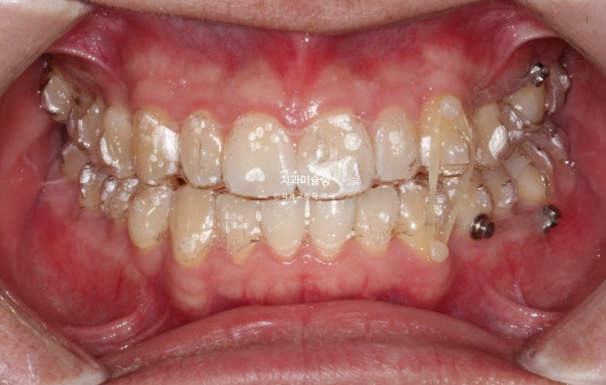

24.11

위 아래 중심선은 정확히 맞고

어금니 교합관계도 1급 입니다.

모든게 좋지만 환자분의 요구사항도 있었고 완성도를 위해 재제작을 1회 더했습니다.

11개 추가장치를 모두 낀 후 25년 6월 치료를 마무리 합니다.

이제 왜소치 무삭제 라미네이트가 들어갈 차례 입니다.